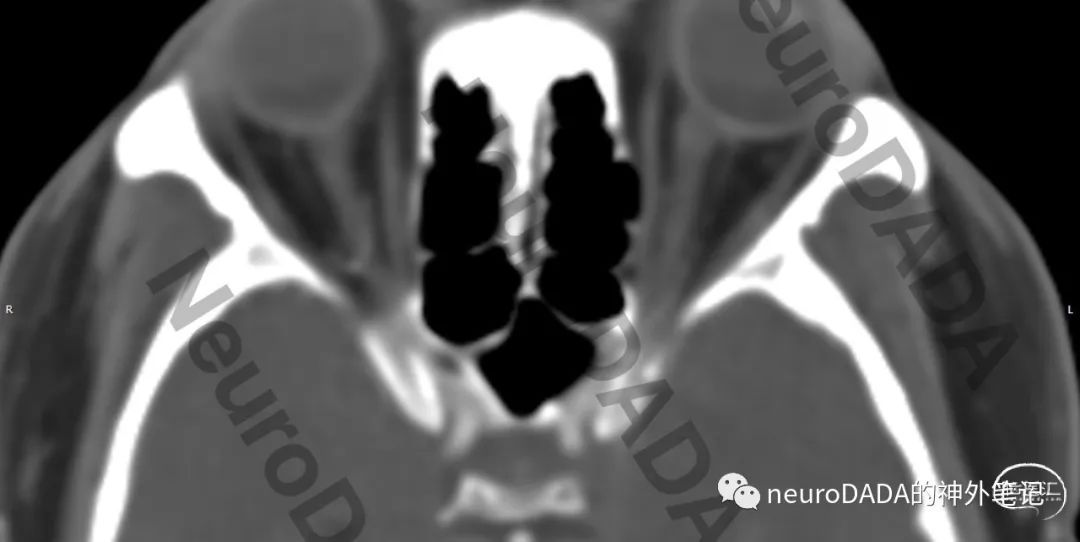

颅骨CT可见双侧颞骨、枕骨骨折,左侧骨折线从外耳道顶壁横跨鼓室、岩骨外侧到达蝶鳞岩交汇处。右侧骨折线位于岩骨外侧和枕骨鳞部,所幸无右侧颅神经损伤表现。眶上裂、眼眶均未见骨折。